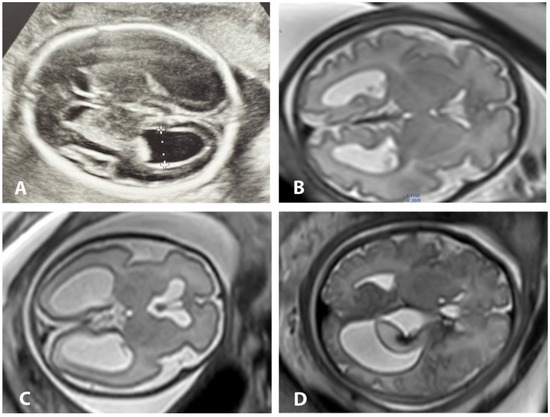

Figure 1. Axial US and MRI images of various degrees of ventriculomegaly. Ultrasonographic image at 28 GW with reverberation artifacts (A). Axial MR images of fetal brain with mild bilateral VM at 31 GW (B), moderate bilateral VM at 29 GW (C) and severe unilateral VM with choroid plexus papilloma hemorrhage (D).

All patients were examined in supine position with a pillow under the knees without the need for a left lateral decubitus position to prevent inferior vena cava compression syndrome. To reduce claustrophobia, patients were scanned feet first with the uterus centered in the bore. No sedation was required. Patients were scanned using 1.5T Signa (GE Healthcare, Chicago, IL, USA) and 3T Ingenia (Philips Healthcare, Amsterdam, The Netherlands) superconducting systems. A 32-channel surface coil was wrapped over the abdomen of the patient in order to place the uterus between the tabletop and the surface coil while using 3T MRI. In 1.5T, an 8-element phased-array surface coil was positioned over the abdomen. The entire uterus was localized with a large field of view covering the cervical length and the entire placenta. Images of the entire uterus in axial, sagittal and coronal planes were captured using T2-weighted half-Fourier single-shot fast spin echo (ssFSE) and turbo spin echo (ssTSE), with large field-of-view and slice thickness ranging between 3 mm and 4 mm, enabling the determination of fetal situs and right-to-left side orientation. T1 sequences were routinely used to exclude hemorrhage or meconium content and were not used for volumetric postprocessing purposes. In selected cases, additional advanced MRI techniques such as echoplanar imaging (EPI) and diffusion-weighted imaging (DWI) sequences were included in the standard protocol to rule out concomitant pathology, but not for the volumetric and segmentation analysis. We used ssFSE in 1.5T and ssTSE in 3T sequences in three planes for the fetus, with the following parameters: field-of-view from 24 × 18 for the fetal head up to 40 × 40 cm for the entire fetus; matrix 512 × 256, 296 × 246, 256 × 256; slice thickness 3 mm and 4 mm; intersection gap 0 mm; single-shot sequence acquisition time 29–56 s for 25–40 slices; number of excitations (NEX) −1 and flip-angle 70°. The TR/TE parameters were 2300/70 ms in 3T and 1360/89 ms in 1.5T. The scanning parameters correspond to the routine scanning protocol in clinical use, and these were not adjusted for the purposes of volumetry in the present study. All the sequences were performed with no breath-holding, assuring optimal maternal comfort during imaging. The overall duration of the scanning time using ssFSE and ssTSE sequences ranged from 6 to 20 min in both 1.5T and 3T, including localizer and repeated sequences due to fetal motion or adjustment for better anatomical orientation. All MR studies were performed by an experienced technologist trained in fetal MRI, and all images were reviewed simultaneously by an experienced radiologist before the end of the exam in order to further reduce the total exposure time. After completion of the exam, a radiologist with 10 years of experience in fetal MRI together with a resident performed independent and double-blinded standardized bi-dimensional and volumetric measurements of the lateral ventricle sizes at the level of the atrium where both third ventricle and posterior basal ganglia were visible, perpendicular to the ventricular long axis. Both observers classified the degree of dilation (mild, moderate, severe) and reported additional (if any) CNS abnormalities (Figure 1).